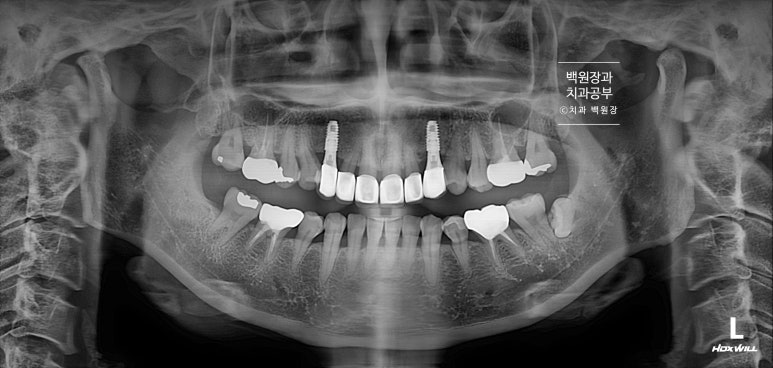

파노라마 엑스레이에서 확실히 확인할 수 있는데요,

똑같이 6개의 앞니를 별로 표시해 보았습니다.

빨간색으로 표시한 두 개의 송곳니 모두 치근우식이 있는 것을 관찰할 수 있습니다. 뿌리에 충치가 심했어요.